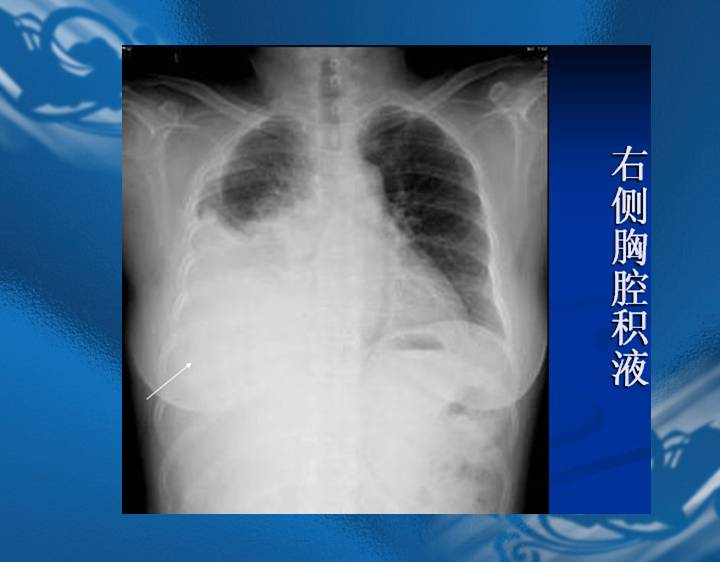

执业医师资格考试“实践技能”影像学辅导资料